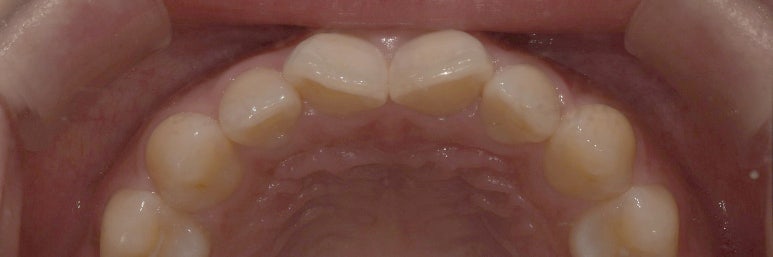

라미네이트 치료 전 모습입니다.

촬영일자: 2023-05-10

이렇게 치아 안쪽 사진을 보면 앞니 2개가 틀어져있는 것이 보이시죠?

이 앞니때문에 원래는 교정을 해야하나 아니면 라미네이트를 해야하나 고민이 많았습니다.

그래서 저희 원장님들께 여쭤보니 제 치아는 만약 교정을 해서 틀어진 부분을 바로잡으면

앞니 2개가 너무 커보일 수 있어서

제가 생각하는 가지런하고 예쁜 치아를 만들기는 어렵다고 하시더라구요 ㅠㅠ

그리고 교정을 하게 될 경우 공간이 좁아서 발치를 해야할 가능성도 있고,

기간도 약 2년 정도는 걸릴 것을 예상해야 하기 때문에

교정보다는 라미네이트를 선택하게 되었고, 개수는 4개로 하기로 했습니다.